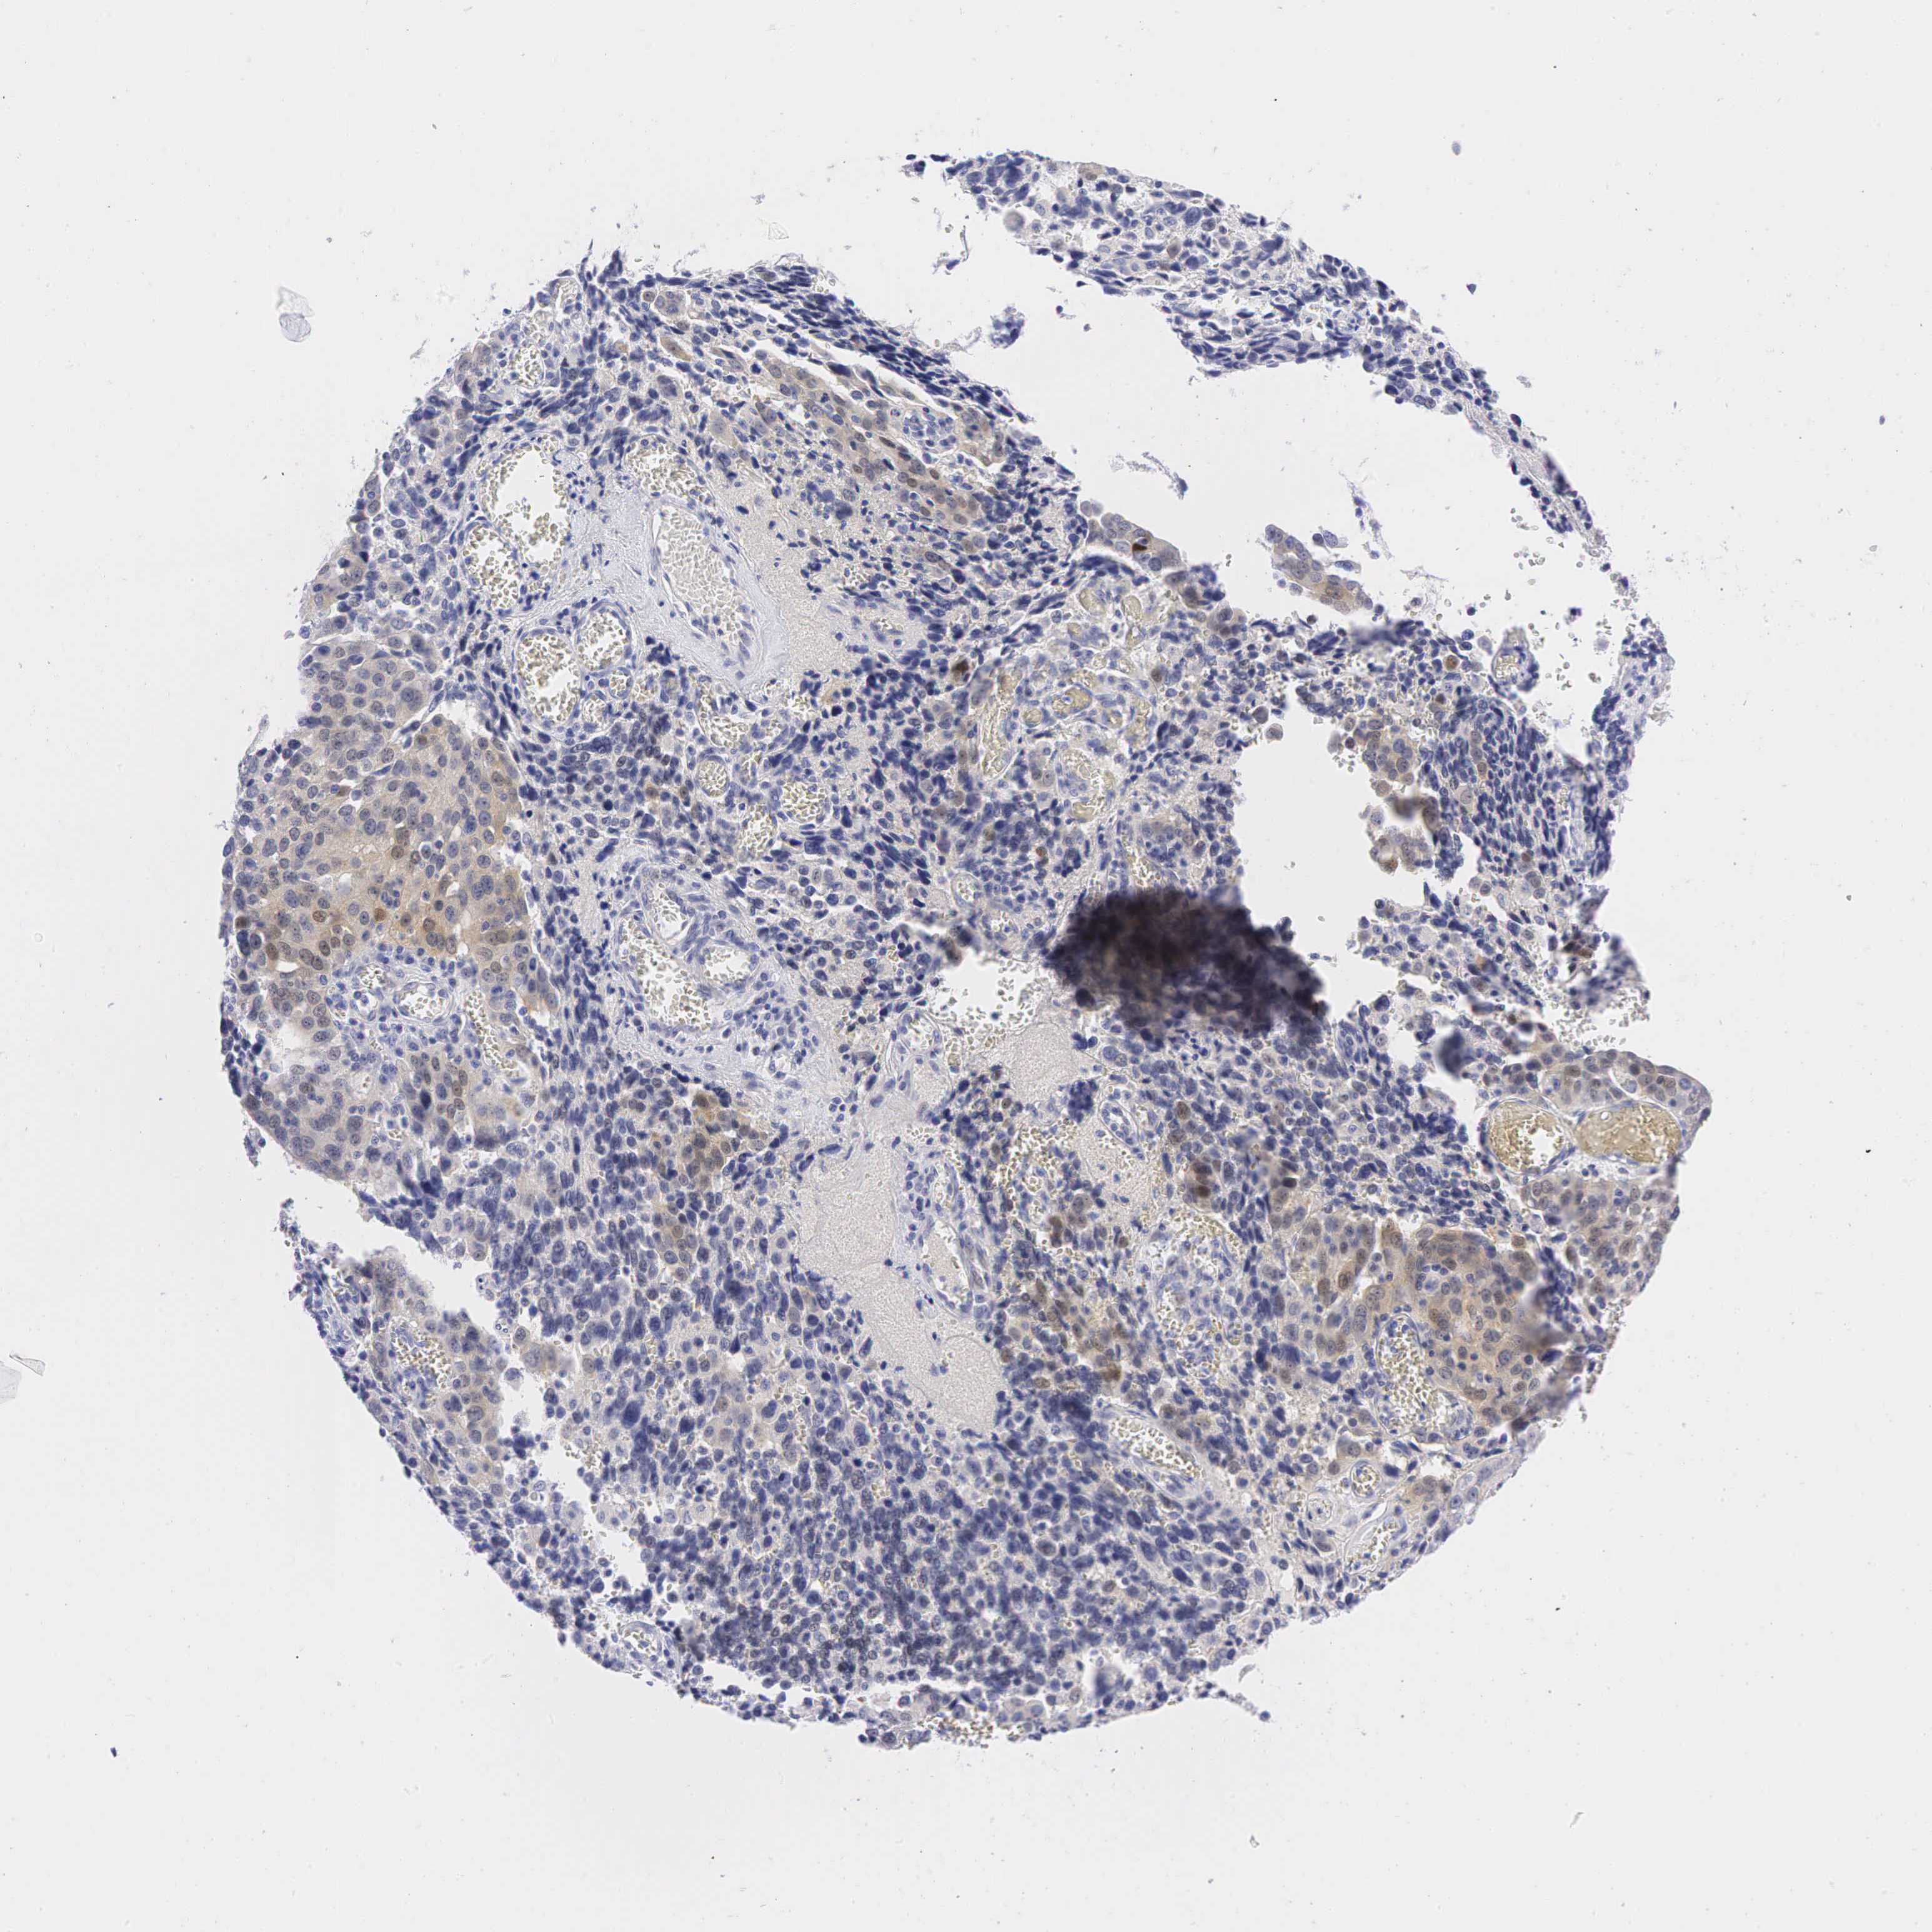

OVARIAN CANCER - Protein expressioni

A mouse-over function shows sample information and annotation data. Click on an image to view it in a full screen mode. Samples can be filtered based on level of antibody staining by selecting one or several of the following categories: high, medium, low and not detected. The assay and annotation is described here.

Note that samples used for immunohistochemistry by the Human Protein Atlas do not correspond to samples in the TCGA dataset.

Antibody stainingi

Antibody staining in the annotated cell types in the current human tissue is reported as not detected, low, medium, or high, based on conventional immunohistochemistry profiling in selected tissues. This score is based on the combination of the staining intensity and fraction of stained cells.

Each image is clickable and will lead to virtual microscopy that enables deeper exploration of all samples and also displays staining intensity scores, fraction scores and subcellular localization as well as patient and tissue information for each sample.

Antibody CAB000001

Antibody CAB065764

Staining

High

Medium

Low

Not detected

Intensity

Strong

Moderate

Weak

Negative

Quantity

>75%

75%-25%

<25%

None

Location

Nuclear

Cytoplasmic/membranous

Cytoplasmic/membranous,nuclear

Cystadenocarcinoma, mucinous, NOS

Carcinoma, endometroid

Cystadenocarcinoma, serous, NOS

Adenocarcinoma, NOS